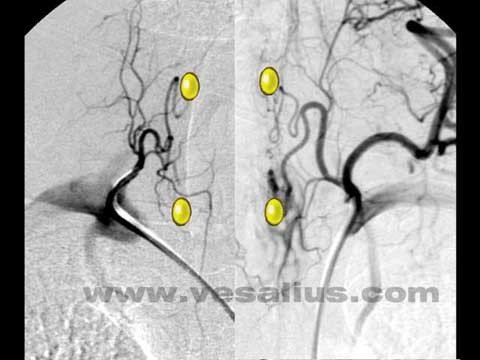

Arterial qan təchizi

Paratiroid vəzlərin qan təchizatı əsasən terminaldır. Yuxarı və aşağı vəzləri a.thyroidea inferior təmin edir. Aşağı vəzlərin 10%-i yuxarı qalxanabənzər arteriyanın şaxəsi ilə də qidalanır.

- Sestamibi ssintiqrafiya metodu 99mTc – izotopların (MİBİ) toxumada toplanma effektliyinə əsaslanır. MİBİ-nin anormal paratiroidlərin lokalizasiyasını aşkar etmə həssaslığı USM-dən daha yüksək olub 68-93%-dır.

- SPECT/KT (Single photon emission computed tomography) əsasən dərin, kiçik, ektopik və mediastinal lokalizasiyalı pataloji ocağı təyin etməyə imkan verir. Bu müayinənin həssaslığı 95%-dir.

- Qamma ötürücü – əməliyyat önü MİBİ ssintiqrafiya ilə paratiroid törəməsi müəyyən edilən xəstələrdə tətbiq olunur. Paratiroid vəzində tutulan sestamibidən yayılan qamma şüaların ötürücü vasitəsilə tutulması prinsipinə əsaslanır.

- Sürətli PTH ölçülməsi – son illərdə paratiroidektomiyanın yetərli olub-olmamasını müəyyən etmək üçün əməliyyat zamanı sürətli parathormonun səviyyəsi ölçülür. Paratiroid vəz çıxarıldıqdan 10 dəqiqə sonra PTH səviyyəsi əməliyyatönü dövrdə ölçülən ən yüksək PTH səviyyəsinin 50% nisbətində azalmasına əsaslanır. Bu zaman başqa anormal vəz olmadığı müəyyənləşir və əməliyyat tamamlanır.

Görüntüləmə rəhbərliyi ilə icra edilən minimal invaziv paratiroidektomiya yeni bir cərrahi üsuldur. Əməliyyat öncə paratiroidi təyin etmək üçün radiometriya metodundan istifadə olunur. Bunun üçün əməliyyatdan 2 saat əvvəl vena daxilinə 18 mCİ 99mTc vurulur. Qamma prob yardımı ilə kəsik yeri müəyyənləşdirilir və adenomanın yeri təyin olunur. Bu üsul qalxanabənzər vəz olmadığı, təkrar əməliyyat və ya ektopik paratiroid adenomu olanlarda daha faydalı olur.